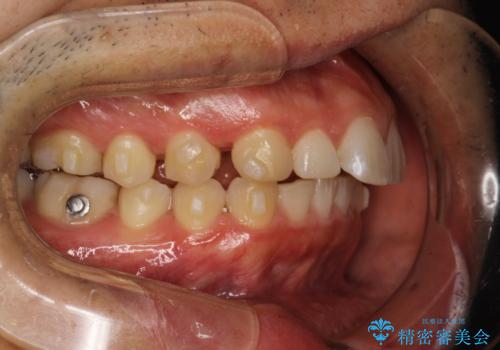

- 出っ歯を主訴に来院されました。

上の歯が全体的に下の歯の位置に比べると前方に位置しており、上の前歯が前方に傾斜している状態でした。

上の奥歯を後方に移動して、隙間を作り、前歯を引っ込める計画としました。